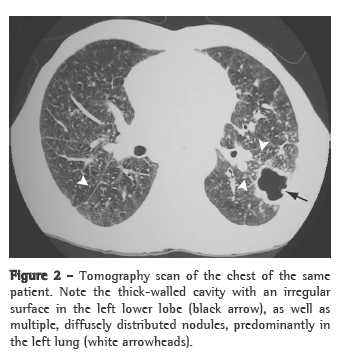

As an initial additional evaluation, it is recommended that sputum smear microscopy and sputum culture (induced sputum culture, if necessary, since it has good sensitivity) be performed, as well as chest X-ray,(23,26) as shown in Figure 1. In cases in which there are still doubts about the presence of active tuberculosis, bronchoscopy with BAL can be used, in conjunction with transbronchial biopsy when possible; biopsies significantly increase the diagnostic yield of the test, even in patients whose sputum and BAL are negative for mycobacteria.(27)

Patterns suggestive of silicotuberculosis have also been recognized on chest CT scans. The principal findings consistent with active tuberculosis superimposed on silicosis are thick-walled cavities (Figure 2), consolidations, images presenting a tree-in-bud pattern, nodular image asymmetry, and rapid disease progression.(26,28,29).